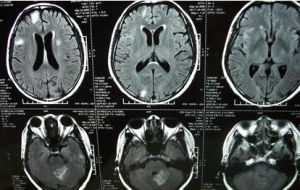

腦脊液檢查外觀清亮,壓力正常或稍高,白細胞數增高,多數在300—500/立方毫米,偶可超過1000—2000個,早期中性細胞增多。從第二病日以後,以淋巴細胞為主,有時可達80%一100%。蛋白含量稍高,糖及氯化物正常。以上變化若在腮腺腫大前不易作出病原診斷,從腦脊液分離病毒是最可靠的診斷依據。近年來,用酶聯免疫吸附測定法檢測腦脊液特異性免疫球蛋白M抗體可協助確診本病。